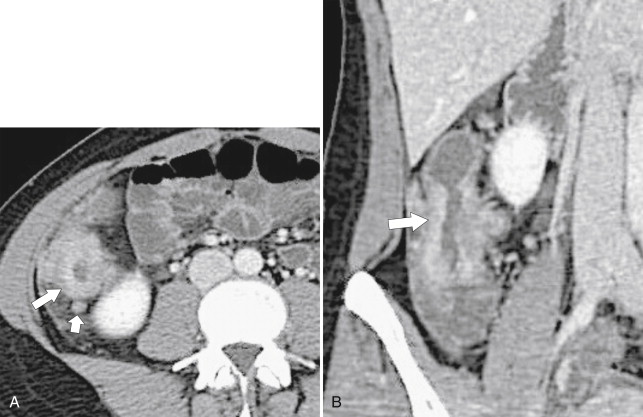

Ultrasound (US) sometimes shows a hypoechoic cystic mass with a thick wall, which has an echogenic outer layer and hypoechoic inner layer. On BE the cyst produces a mass effect of adjacent bowel and on CT appears as a nonenhancing mass, compressing or displacing the adjacent bowel, which may contain simple fluid, hemorrhage, or proteinaceous fluid ( Fig. 5-4 ). On MRI the enteric cysts are usually hyperintense on T2-weighted imaging, reflecting their cystic nature ( Fig. 5-5 ). Because many duplication cysts contain ectopic gastric mucosa, a Tc-99m pertechnetate radionuclide study can often show radionuclide uptake, which can also be observed within a Meckel diverticulum for the same reason.

Figure 5-4, Axial contrast-enhanced CT in a 46-year-old woman with a 4.5-cm homogeneous pararectal mass ( arrow ) caused by rectal enteric duplication.

Figure 5-5, Axial ( A ) and sagittal ( B ) T2-weighted imaging in a 30-year-old woman with a cystic 4.5-cm mass ( arrows ) in a posterolateral perirectal location resulting from a rectal duplication cyst.